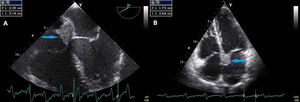

A 57-year-old man was referred to the hospital for evaluation of a right hilar lung mass discovered on a chest X-ray performed because of a persistent cough, increasing effort dyspnea and deterioration of the general condition. He has no medical history and had smoked 35 packs a year. On the admission, physical examination showed a slow heart rate at 40 beats per minute. The electrocardiogram showed a complete atrioventricular block. On echocardiography, a 26×17mm mass was noted in the basal area of the atrial septum without interfering with the mitral valve function (Fig. 1). A thoracic computed tomography (CT) scan revealed a right pulmonary hilum mass with mediastinal and peritoneal lymphadenopathy, adrenal metastasis, and a low-density mass located on the interatrial septum (Fig. 2). Fiberoptic bronchoscopy showed stenosis with mucosal tumor infiltration in the right upper lobe bronchus. The bronchial biopsy revealed a moderately differentiated adenocarcinoma. Based on these findings, the atrioventricular block was associated with interatrial septum metastasis of the lung adenocarcinoma. A pacemaker was implanted and pemetrexed platinum chemotherapy was started.

Myocardial metastases from lung cancer are uncommon. Electrocardiographic abnormalities in include arrhythmia, conduction disturbances and complete atrioventricular blocks.1 Echocardiography is the best non invasive imaging technique for cardiac tumors detection. Cardiac magnetic resonance imaging (MRI), used to determine tumor morphology and to predict malignancy, has higher temporal resolution and further tissue characterization than cardiac computed tomography (CT). CT is an alternative to cardiac MRI and echocardiography.2